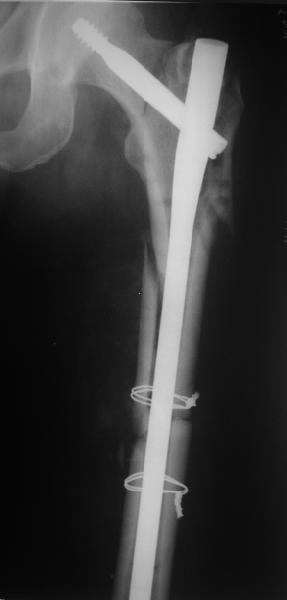

ВБ> Длинная гамма?

ВБ> Зона раскола во время моей ревизии проходит по боковой поверхности как

ВБ> раз в зоне введения шеечного винта (картина как топор разрубил полено

Зона введения и вообще латеральная стенка тут не имеет значения, поскольку угловая стабильность обеспечивается самим фиксатором.

В общем, сделали. См. приложение.

Длина и из-за этого ось получились не совсем такие, как хотелось бы, все-таки срок после той операции уже 6 недель. Может быть, стоило провести дистракцию аппаратом неделю-другую. Заранее спасибо за комментарии и критику.